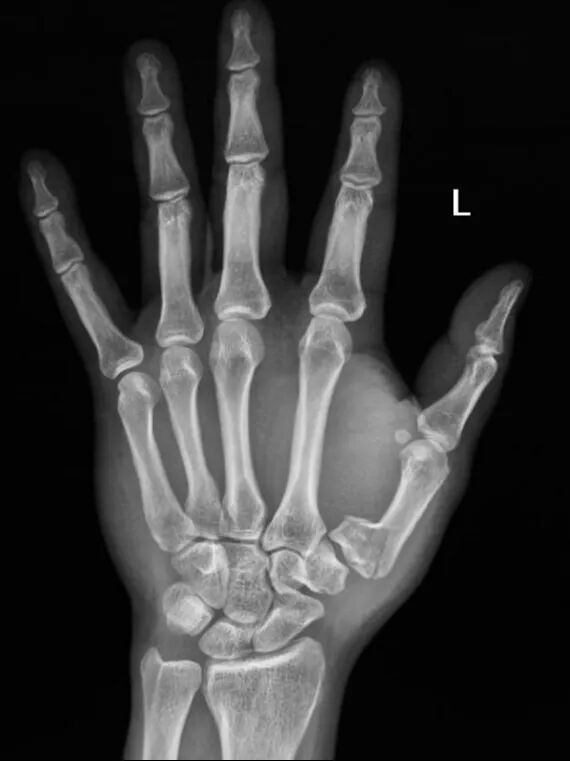

患者是39歲男性,因摔倒導致左手第一掌骨基底部骨折。

手術前左手正斜位片